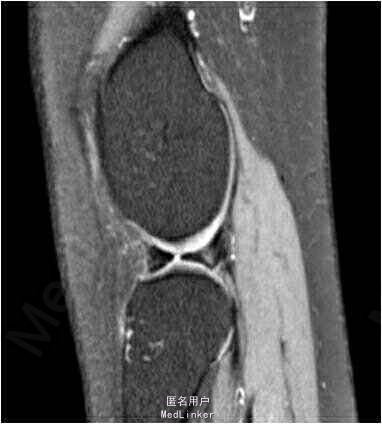

患者女,30岁,因“摔伤致右膝关节反复疼痛1年余”。患者1年前不慎摔伤后右膝关节出现反复疼痛,上下楼梯时加重。1年以来患者疼痛症状反复,现患者为求进一步诊治前来我院就诊,余未见明显异常。

查体:双下肢无畸形,右膝关节关节间隙压痛,麦氏征(+),肢端血运、感觉、活动正常。左下肢及双上肢其余关节未见明显异常。MRI检查提示:右膝关节半月板损伤伴囊肿形成。

诊断:右膝外侧半月板后角损伤伴囊肿形成。拟行手术:右膝关节镜检,囊肿清理,半月板修补。